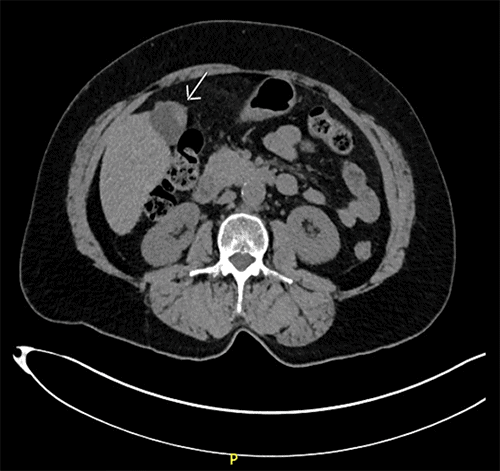

On original examination, the patient appeared well, with no abdominal tenderness, distention, guarding, masses, or evident jaundice. Initial laboratory evaluation revealed a total bilirubin of <0.2 mg/dL, alkaline phosphatase of 73 units/L, alanine aminotransferase (ALT) of 201 units/L, and aspartate aminotransferase (AST) of 290 units/L. Carcinoembryonic antigen (CEA) was elevated at 7.8 ng/mL, while CA 19-9 was within normal limits. A complete blood count and complete metabolic panel were unremarkable. Initial CT of the abdomen and pelvis demonstrated focal thickening of the gallbladder wall without pericholecystic stranding (Figure 1).

Figure 1. Abdominopelvic CT Imaging. Published with Permission

(A) Axial CT image demonstrating focal thickening of the gallbladder wall without pericholecystic stranding

(B) Coronal CT image demonstrating focal thickening of the gallbladder wall without pericholecystic stranding